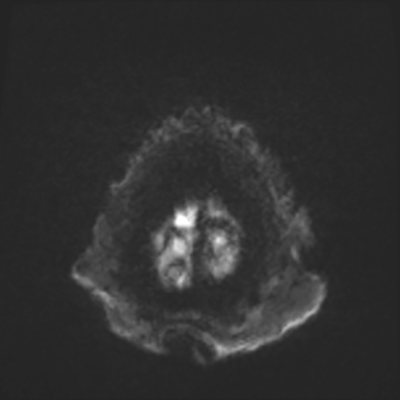

You come back the next day and see how things are going. The patient's electrographic record has shown a moderate encephalopathy (diffuse slowing, disorganization) with frequent right posterior quadrant delta slowing. Based on this result, and an adequately improved clinical examination, you give the okay to proceed with obtaining an MRI of his brain. This is shown below.

MRI brain (DWI)